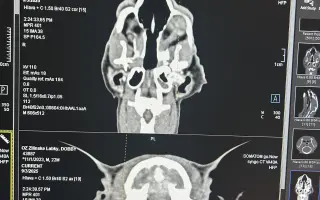

Dobbík podstúpil CT, na základe ktorého bolo možné presne odhadnúť rozsah škôd po infekcii a uskutočniť tak operáciu. Dobček tak hneď na to absolvoval všetky predoperačné vyšetrenia, ktoré mal v poriadku, takže nasledovala operácia samotná.

Ďalším diagnostickým krokom pred nevyhnutnou operáciou je CT vyšetrenie, ktoré odhalí rozsah infekcie. Bez toho by chirurg operoval takpovediac „na slepo“. Samotné CT vyšetrenie stojí 600€ – následne budeme vedieť presnejší cenový odhad operácie – avšak už teraz vieme povedať, že menej ako 800€ podobné zákroky nestoja.